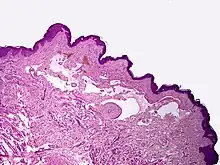

Microscopically, the vesicles in lymphangioma circumscriptum are greatly dilated lymph channels that cause the papillary dermis to expand. They may be associated with acanthosis and hyperkeratosis. There are many channels in the upper dermis which often extend to the subcutis (the deeper layer of the dermis, containing mostly fat and connective tissue). The deeper vessels have large calibers with thick walls which contain smooth muscle. The lumen is filled with lymphatic fluid, but often contains red blood cells, lymphocytes, macrophages, and neutrophils. The channels are lined with flat endothelial cells. The interstitium has many lymphoid cells and shows evidence of fibroplasia (the formation of fibrous tissue). Nodules (A small mass of tissue or aggregation of cells) in cavernous lymphangioma are large, irregular channels in the reticular dermis and subcutaneous tissue that are lined by a single layer of endothelial cells. Also an incomplete layer of smooth muscle also lines the walls of these channels. The stroma consists of loose connective tissue with a lot of inflammatory cells. These tumors usually penetrate muscle. Cystic hygroma is indistinguishable from cavernous lymphangiomas on histology.[4]